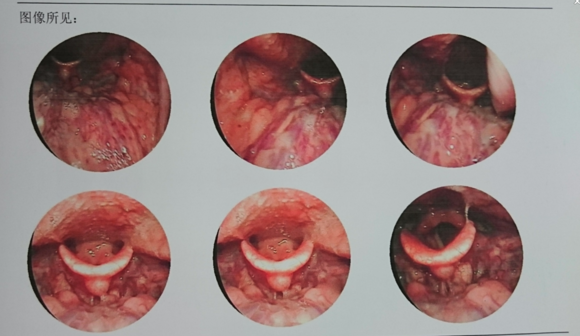

电子鼻咽喉镜检查:发现患者“双侧鼻腔黏膜充血,水肿,双侧中、下鼻甲肥大,鼻中隔偏曲;鼻咽部可见腺样体肥大,阻塞了后鼻孔,表面有分泌物粘附;此外咽部黏膜充血,咽喉部可以看见淋巴滤泡增生;双侧扁桃体肿大。”

诊断结果为:1、慢性扁桃体炎。2、腺样体肥大。3、肥厚性鼻炎